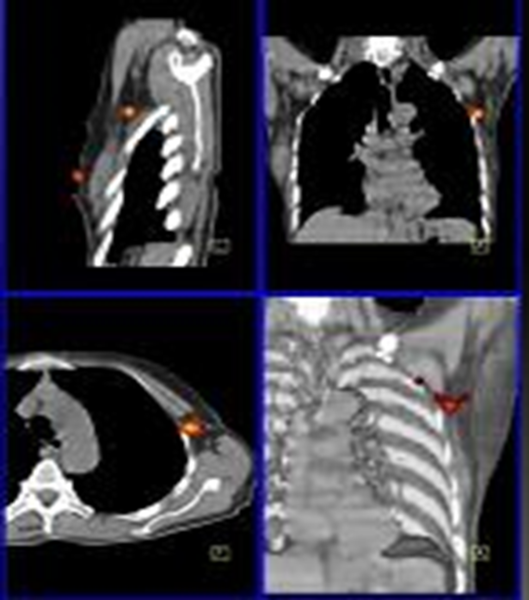

Si, dans le cancer du sein, l’imagerie planaire est souvent suffisante pour déterminer de façon précise la localisation anatomique du ganglion sentinelle, la situation peut être plus délicate dans les cas de mélanomes où le site de drainage lymphatique n’est pas toujours évident et les régions anatomiques complexes. Le SPECT/CT permet alors d’augmenter la précision anatomique en indiquant la profondeur et la localisation précise du ganglion sentinelle.  La connaissance pré-opératoire précise de la localisation anatomique permet de faciliter le geste chirurgical consistant à extraire le ganglion sentinelle pour analyse et de planifier la voie d’abord (fig. 5).

Figure 5 - Cancer du sein : ganglion sentinelle localisé par SPECT/CT